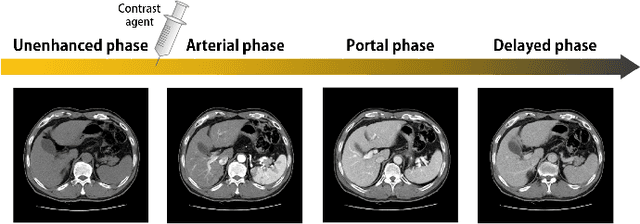

Abstract:Image registration is a fundamental task in medical image analysis. Recently, deep learning based image registration methods have been extensively investigated due to their excellent performance despite the ultra-fast computational time. However, the existing deep learning methods still have limitation in the preservation of original topology during the deformation with registration vector fields. To address this issues, here we present a cycle-consistent deformable image registration. The cycle consistency enhances image registration performance by providing an implicit regularization to preserve topology during the deformation. The proposed method is so flexible that can be applied for both 2D and 3D registration problems for various applications, and can be easily extended to multi-scale implementation to deal with the memory issues in large volume registration. Experimental results on various datasets from medical and non-medical applications demonstrate that the proposed method provides effective and accurate registration on diverse image pairs within a few seconds. Qualitative and quantitative evaluations on deformation fields also verify the effectiveness of the cycle consistency of the proposed method.

Abstract:Medical image registration is one of the key processing steps for biomedical image analysis such as cancer diagnosis. Recently, deep learning based supervised and unsupervised image registration methods have been extensively studied due to its excellent performance in spite of ultra-fast computational time compared to the classical approaches. In this paper, we present a novel unsupervised medical image registration method that trains deep neural network for deformable registration of 3D volumes using a cycle-consistency. Thanks to the cycle consistency, the proposed deep neural networks can take diverse pair of image data with severe deformation for accurate registration. Experimental results using multiphase liver CT images demonstrate that our method provides very precise 3D image registration within a few seconds, resulting in more accurate cancer size estimation.